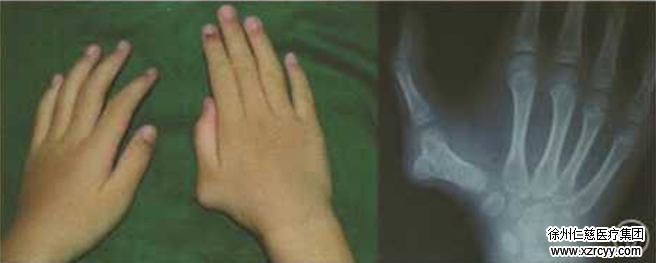

术前检查

然而悬着的心还未放下多久,随着孩子发育长大,新问题出现了——寒寒大拇指外侧产生了新的畸形, 慢慢长出了一个硬疙瘩,而且越长越大。

1月21日,韩先生夫妻便带着寒寒到betway在线登陆手外科就诊。接诊的董自强医生,仔细询问了孩子病情。在综合掌握情况后,根据孩子的实际情况,为其制定了详细治疗方案。告诉韩先生,根据X线检查结果,要先去除膨大的掌骨,再对第1掌骨进行楔形截骨,矫正尺偏畸形,然后将拇短展肌止点重建,关节囊进行修复,维持关节稳定性,加强拇指外展功能。